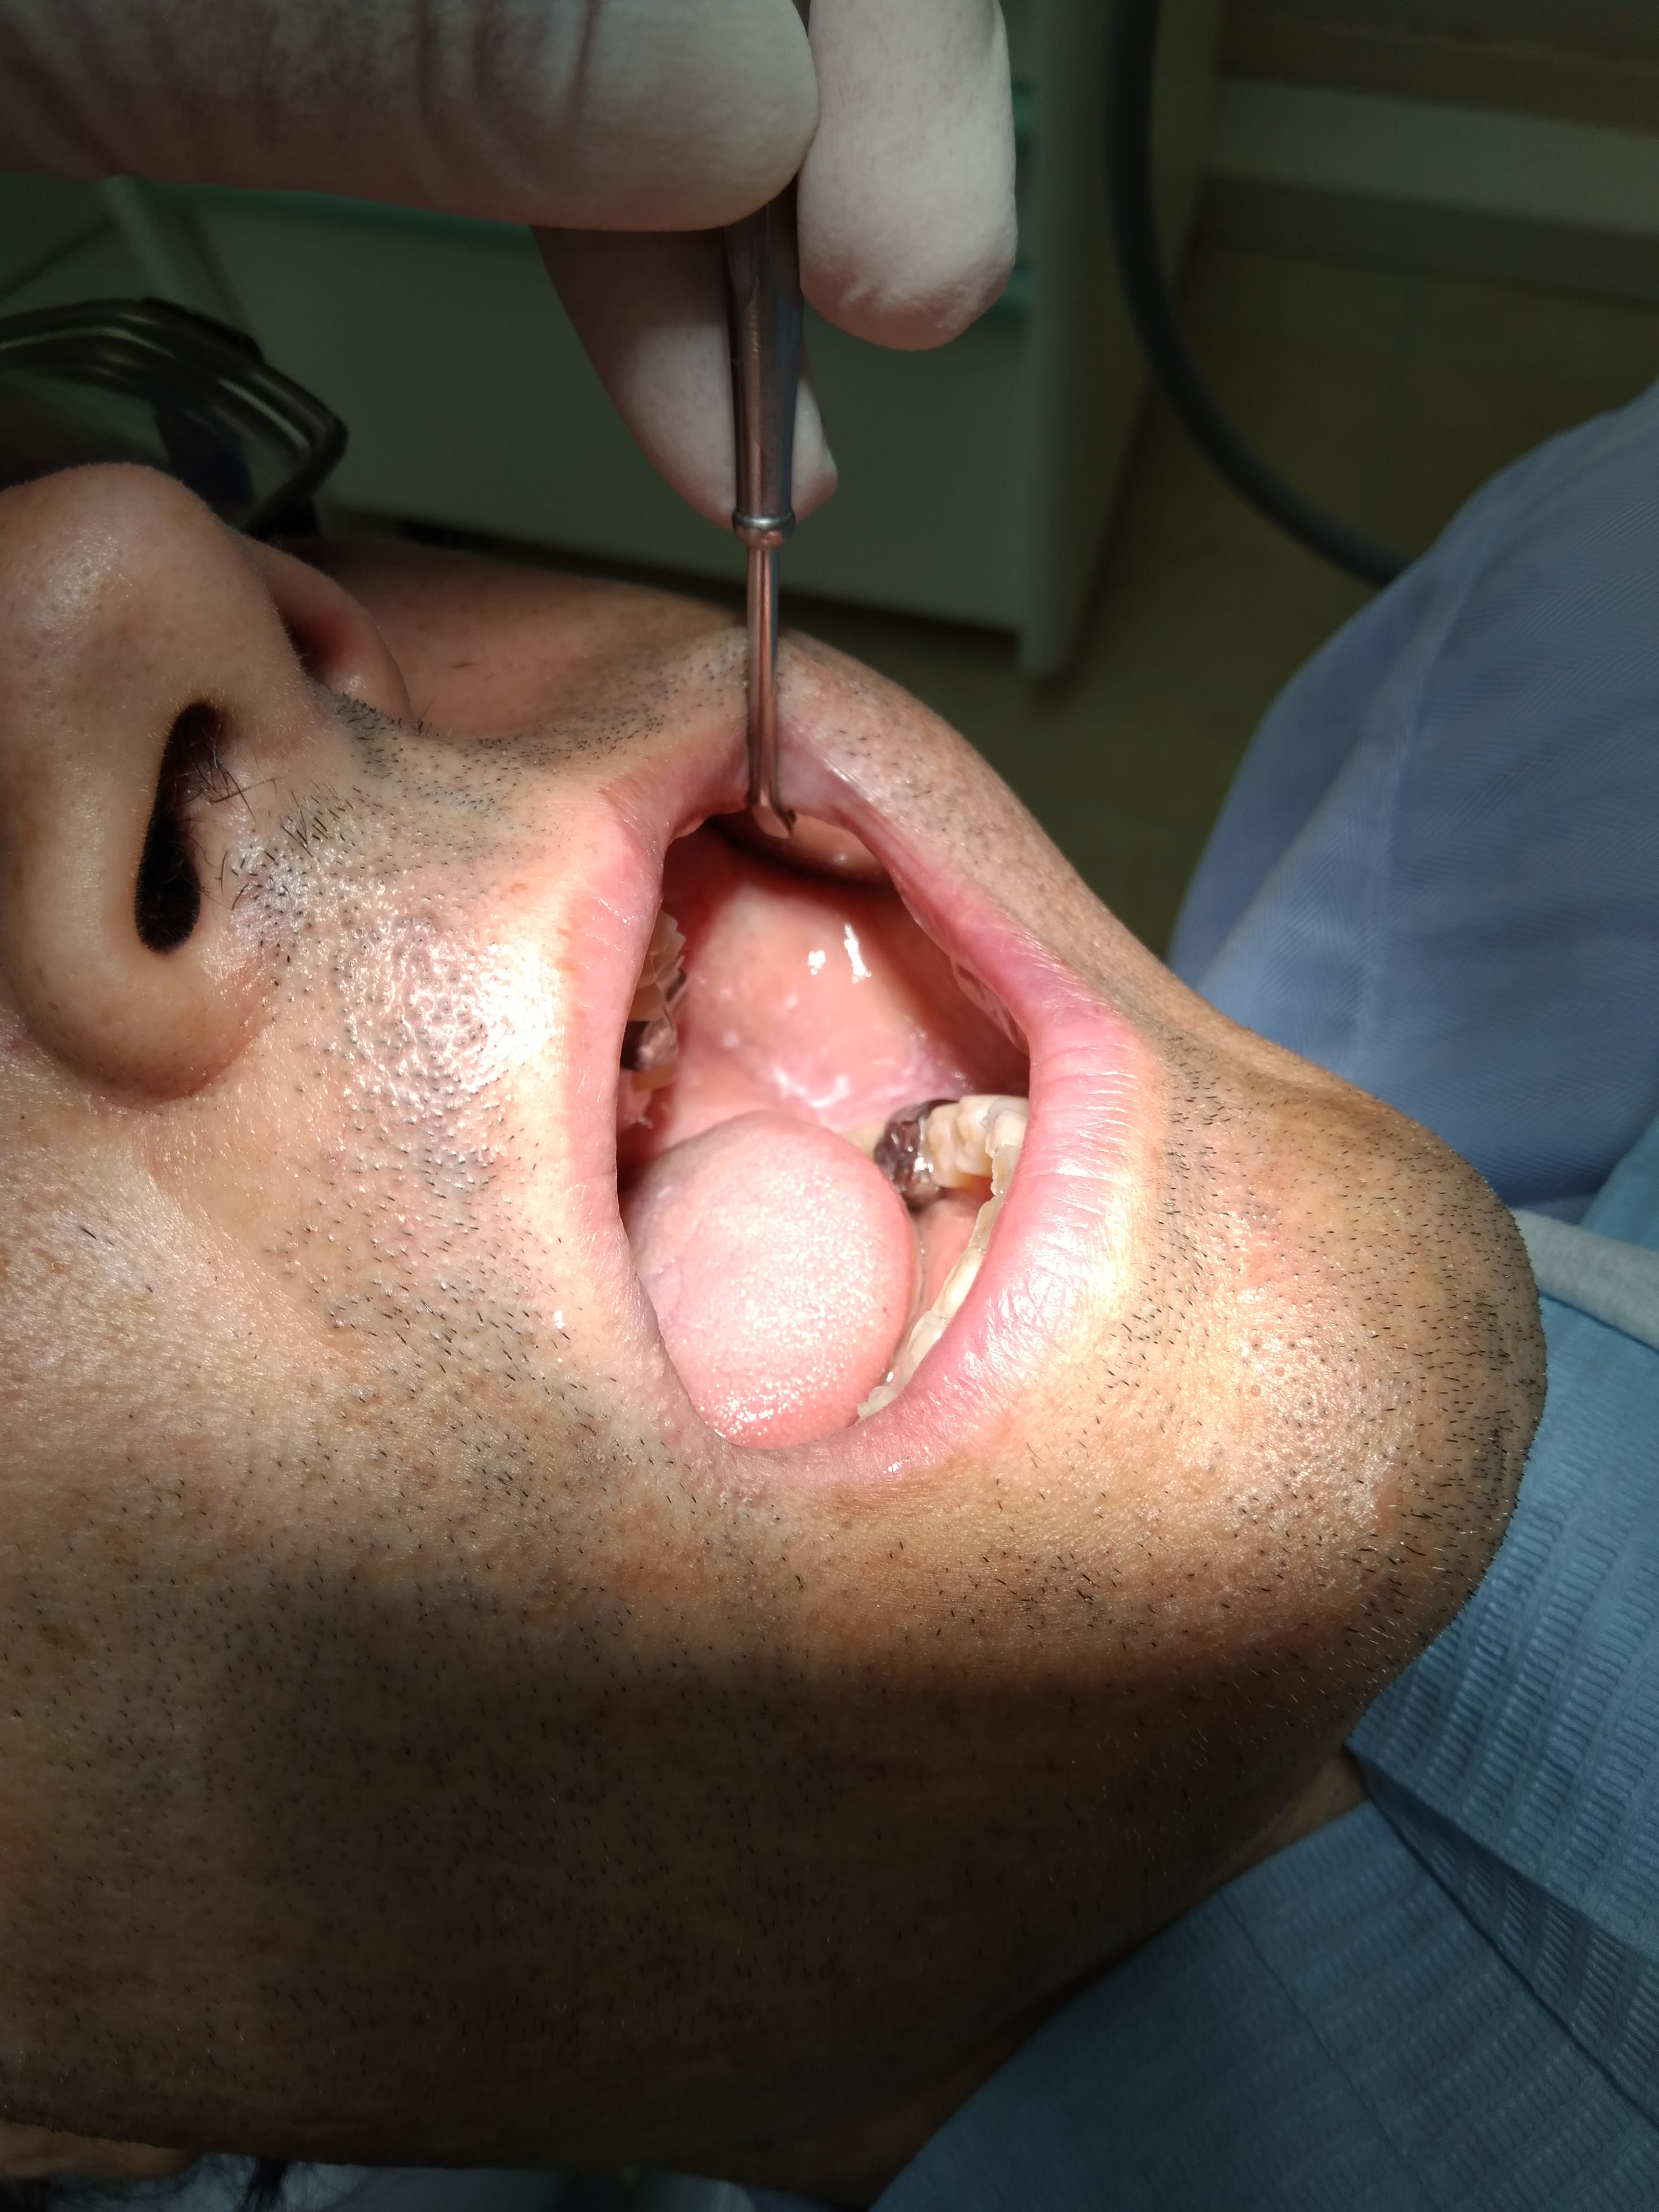

Nan vraiment c'est trop! Fallait pas (venir)...

Son "ex" m'a dit "depuis notre séparation ça a été la dégringolade pour lui"... C'est elle qui me l'a amené... Ah les femmes:-))

Dscf3286 ulx3ie - Eugenol

Dscf3287 ghd4mb - Eugenol

Dscf3288 lwxprq - Eugenol